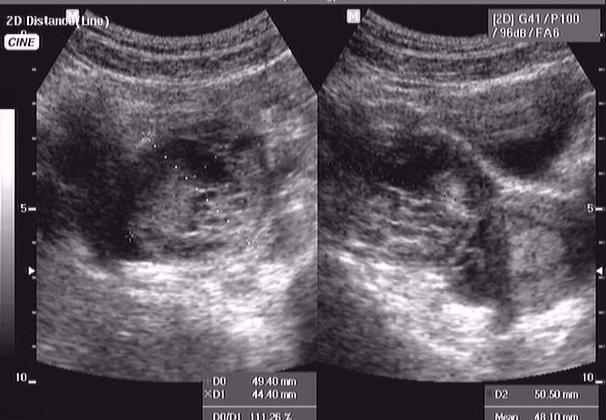

кровоизлияние в кисту яичника

девушка 16 лет, дисменоррея. поступила в хирургию вчера вечером д-з о. аппендицит.